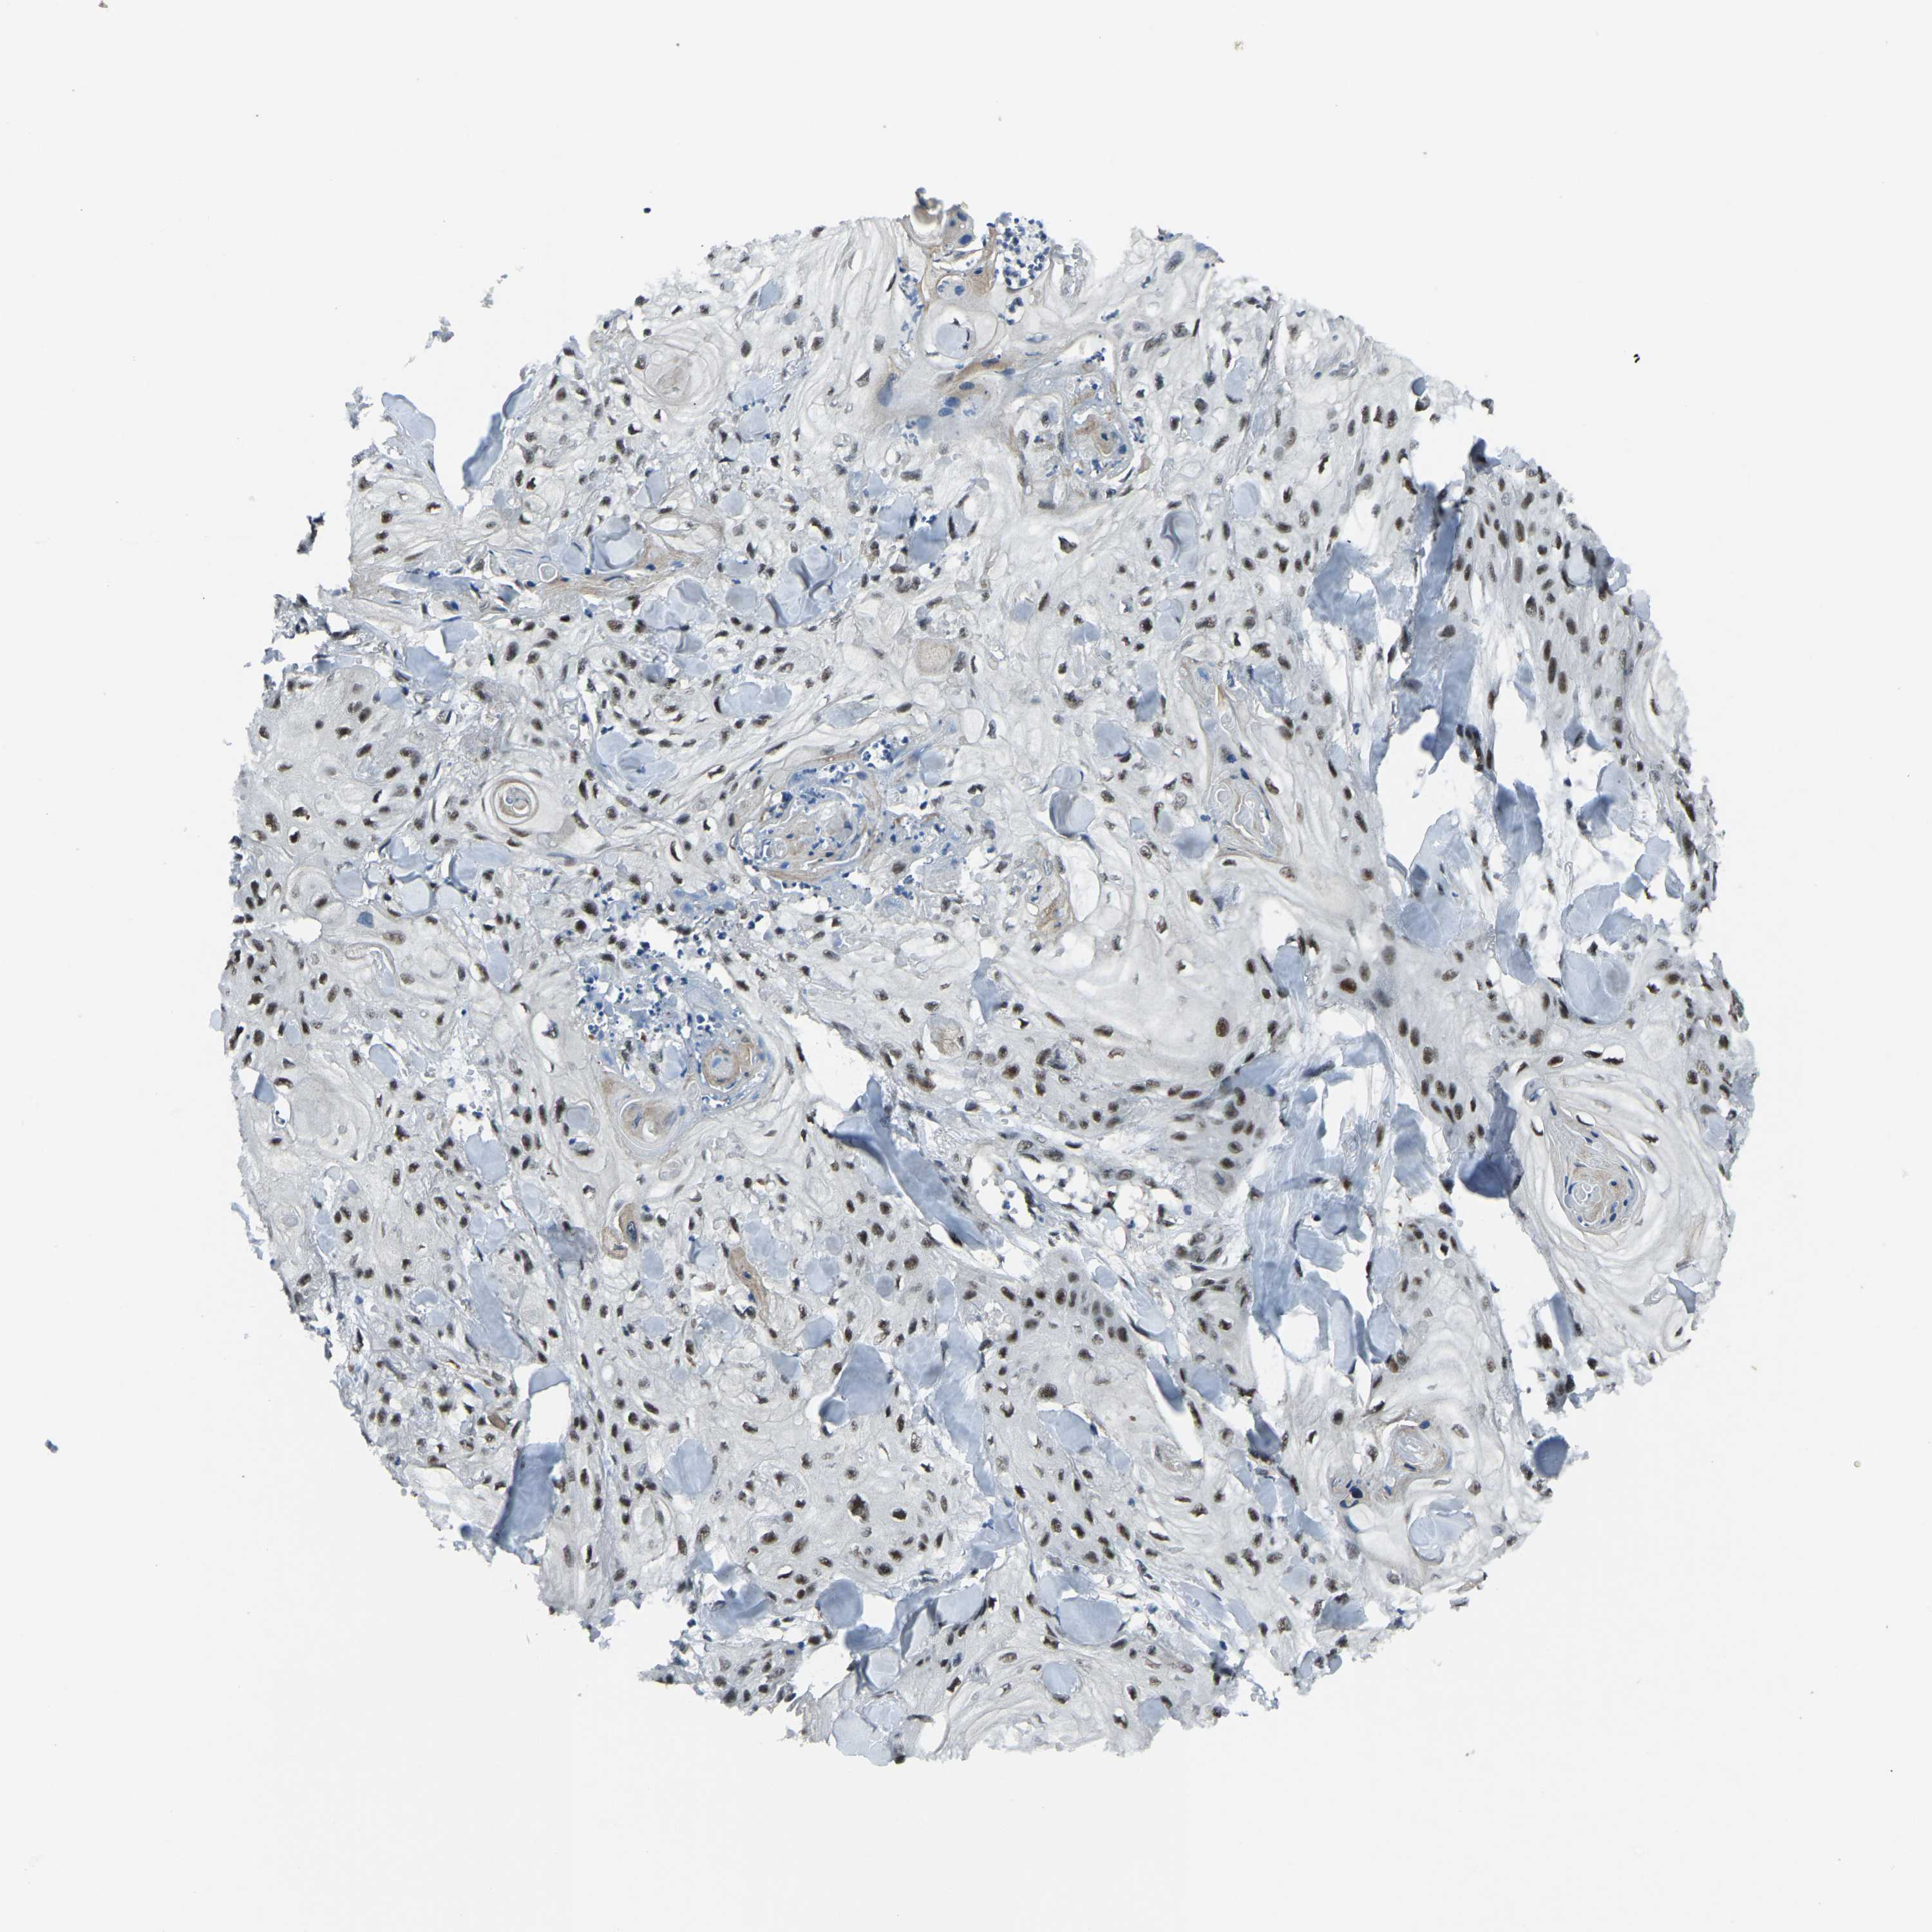

SKIN CANCER - Protein expressioni

A mouse-over function shows sample information and annotation data. Click on an image to view it in a full screen mode. Samples can be filtered based on level of antibody staining by selecting one or several of the following categories: high, medium, low and not detected. The assay and annotation is described here.

Antibody stainingi

Antibody staining in the annotated cell types in the current human tissue is reported as not detected, low, medium, or high, based on conventional immunohistochemistry profiling in selected tissues. This score is based on the combination of the staining intensity and fraction of stained cells.

Each image is clickable and will lead to virtual microscopy that enables deeper exploration of all samples and also displays staining intensity scores, fraction scores and subcellular localization as well as patient and tissue information for each sample.

Antibody HPA019463

Antibody HPA019481

Antibody CAB017151

Staining

High

Medium

Low

Not detected

Intensity

Strong

Moderate

Weak

Negative

Quantity

>75%

75%-25%

<25%

None

Location

Nuclear

Cytoplasmic/membranous

Cytoplasmic/membranous,nuclear

Squamous cell carcinoma, NOS

Squamous cell carcinoma, metastatic, NOS

Squamous cell carcinoma in situ, NOS